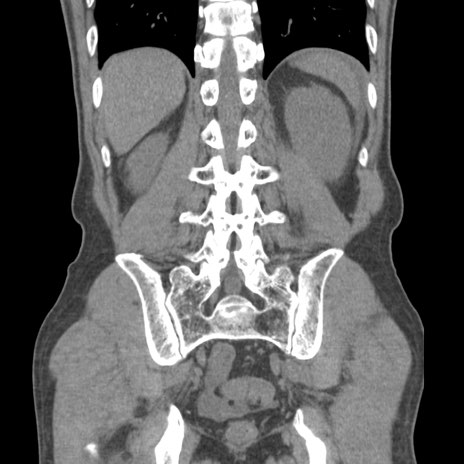

症例56 CT(冠状断像)

脂肪ウインドウ

横断像